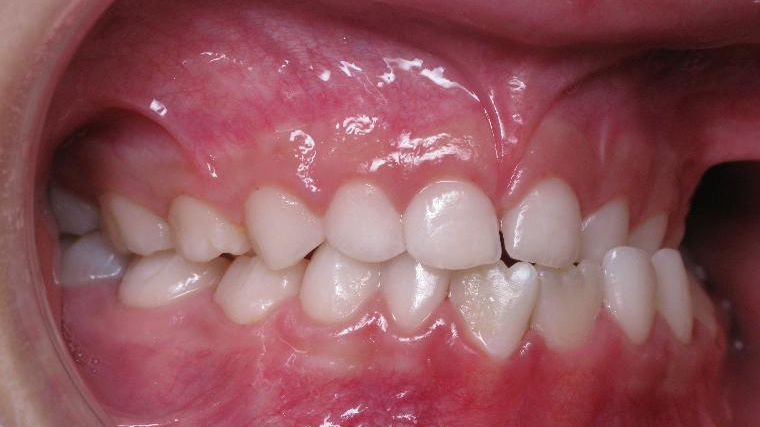

surveillance évolution de la dentition pendant 4 ans

appareillage multibagues pendant 3 ans

surveillance de la dentition par gouttieres nocturne

bilan début et fin de traitement